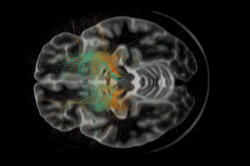

Neuer Blick auf neurologische und psychiatrische Erkrankungen

Im Exzellenzcluster NeuroCure wird Grundlagenforschung in neue Diagnosemethoden und Therapien übersetzt